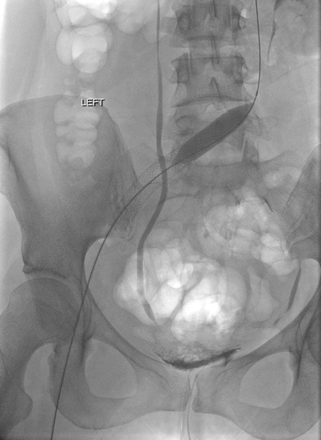

Venograma en posición de decúbito prono donde se muestra un trombo agudo oclusivo que va de la vena poplítea derecha hasta el filtro de VCI.